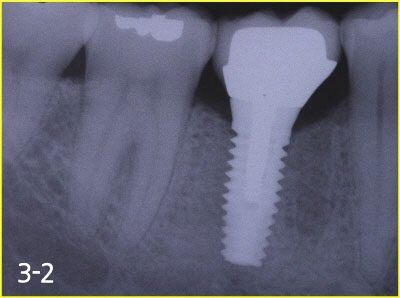

Implant crown was fabricated